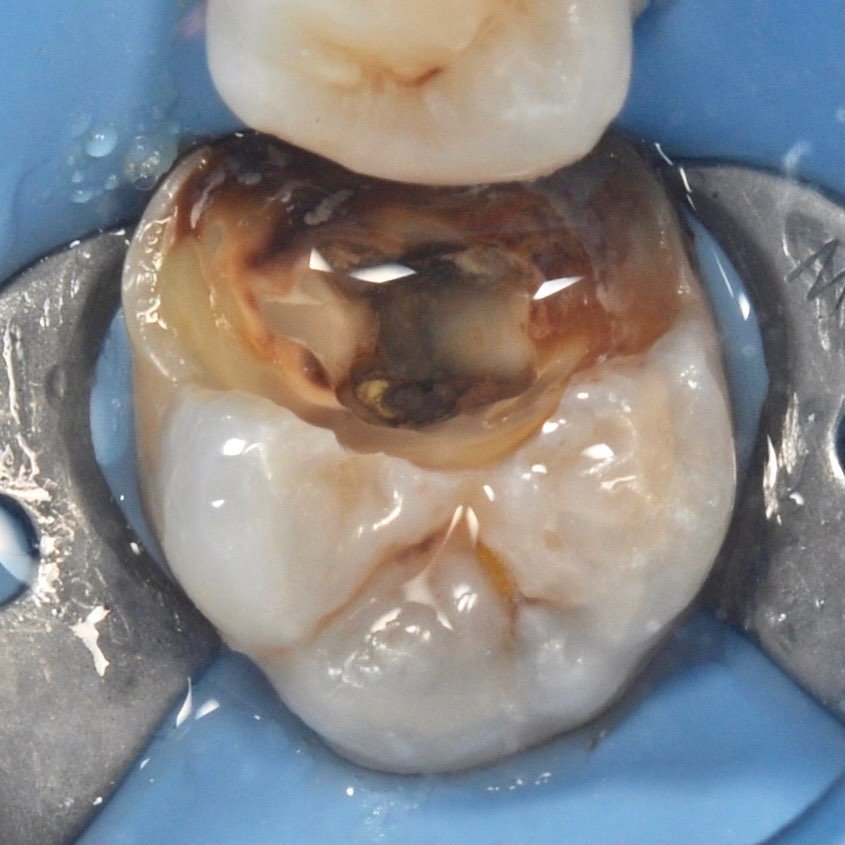

The use of a microscope in dentistry is an ultra-modern direction. Optical instruments allow for constant monitoring of the treatment process, which directly affects the quality of treatment and is aimed at preserving tooth tissues.

The microscope illuminates and enlarges the working field by about 25 times, which helps to accurately determine the anatomical structure of the tooth and restore it with maximum accuracy.

Successful endodontic treatment requires careful preparation, disinfection and sealing of the canals.

• Easily locate the entrance to the canal with maximum preservation of the tooth structure.

• Identify additional canals and anatomical features.

• Control the removal of pulp and organic tissue from the canal, which protects us from secondary infection.